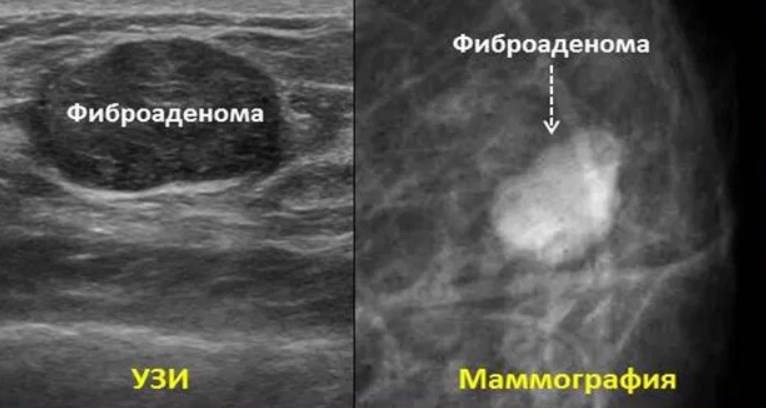

• Фиброаденома. Он состоит из соединительной ткани и эпителиальных клеток. Шустрый, безболезненный, гладкий или неровный.

• Сонография. Базовый безопасный способ исследования молочных желез. Обнаруживает опухоли, очаги воспаления, структурные аномалии. Он более информативен у молодых женщин, так как ткань их груди более плотная и хорошо визуализируется при ультразвуковом исследовании.

• Маммография. Этакая рентгенография. Предпочитается пожилым женщинам. Подтверждает фиброзные изменения, опухолевидные образования. Для повышения информативности его можно дополнить дуктографией. В случае неоднозначных результатов процедуры проводится цифровой томосинтез. Пациентам с кистами проводится пневмоцистография.